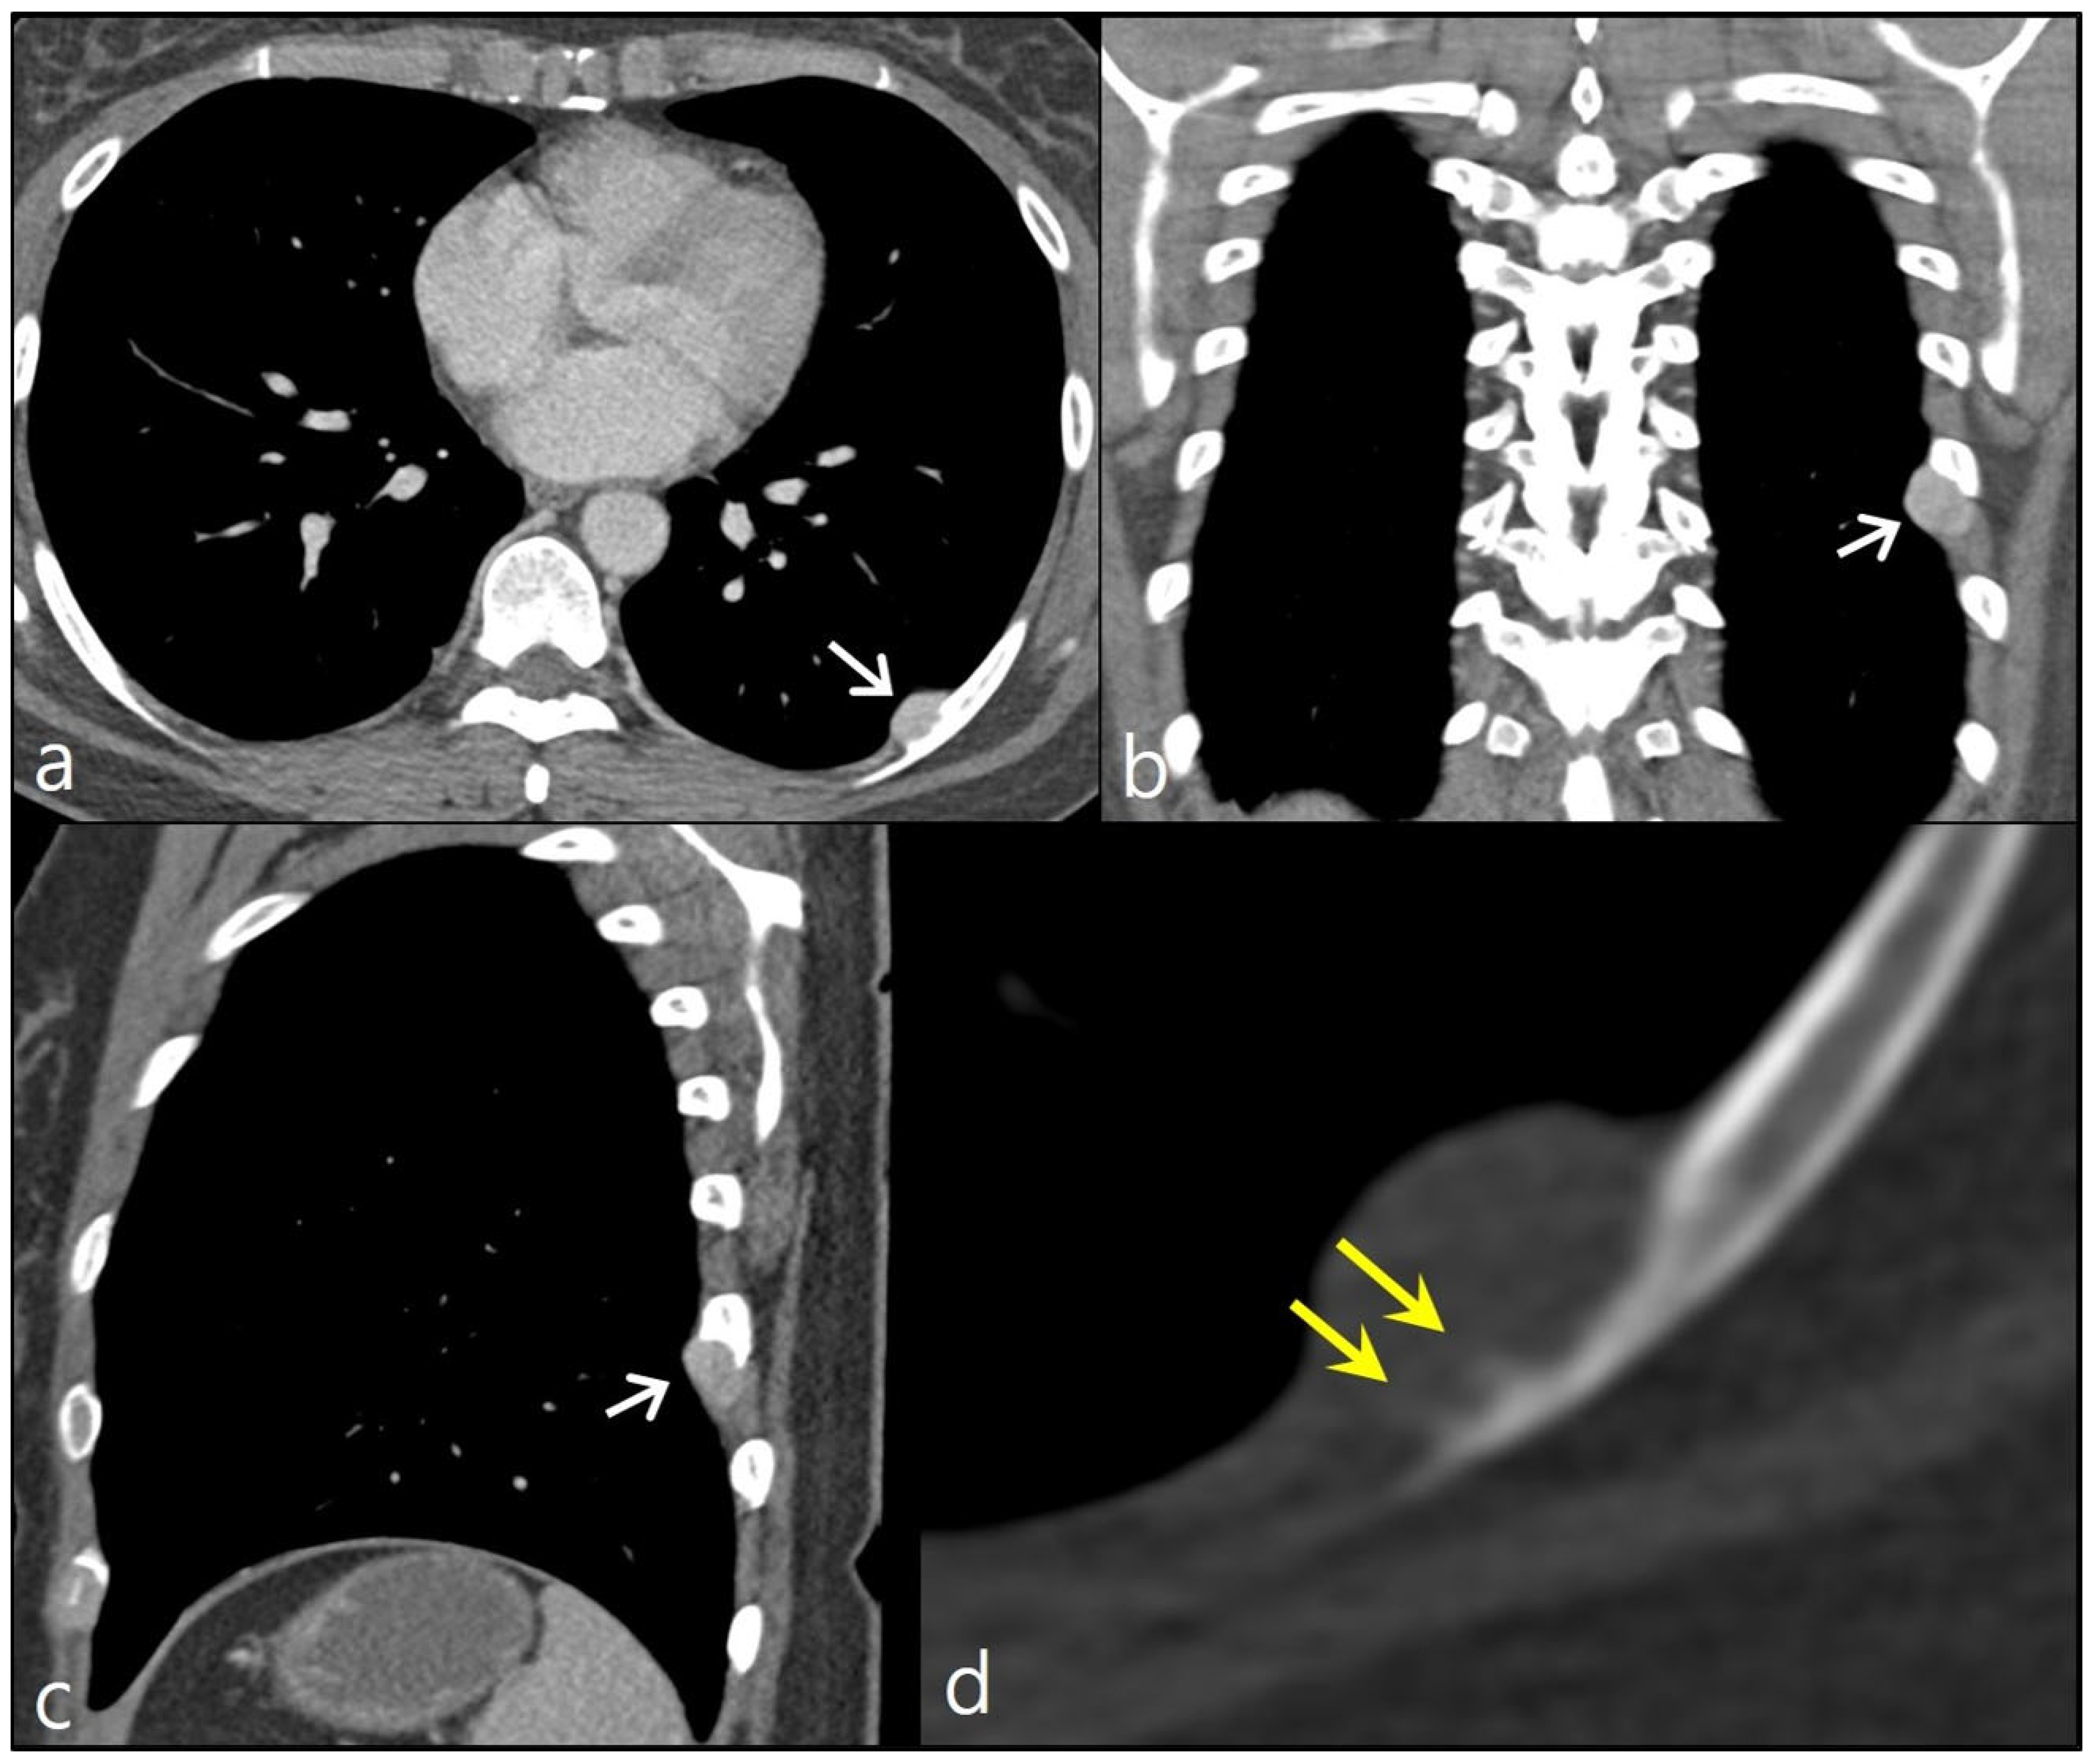

Figure 1.

Chest CT images with contrast enhancement show a well-circumscribed nodule along the inner and inferior aspects of the left eighth posterior rib (arrows in a–c). Focal cortical erosion of the rib is noted. On the magnified image using a bone window setting, bony spicules (double arrow) oriented perpendicularly to the rib cortex were observed, indicating a potential sunburst-like periosteal reaction (d).

A 44-year-old woman visited an outpatient clinic due to a nodular lesion detected on a chest X-ray screening. She did not complain about any symptoms. She was never a smoker. She was previously healthy. She had no notable family history of cancer. According to her chest CT scan, the nodule was an extrapleural lesion located along the inner surface of left eighth posterior rib. It measured about 1.8 cm in its maximum diameter. The nodule showed homogeneous contrast enhancement with a smooth well-demarcated margin. Focal cortical erosion of the left eighth rib was noted. Given the imaging features and the location of the lesion, a neurogenic tumor such as schwannoma was suspected. Nevertheless, upon closer examination of a magnified CT image using a bone window setting, the presence of bony spicules oriented perpendicularly to the rib cortex was observed, indicating a potential sunburst-like periosteal reaction. This finding raises concerns about the likelihood of malignancy (Figure 1).